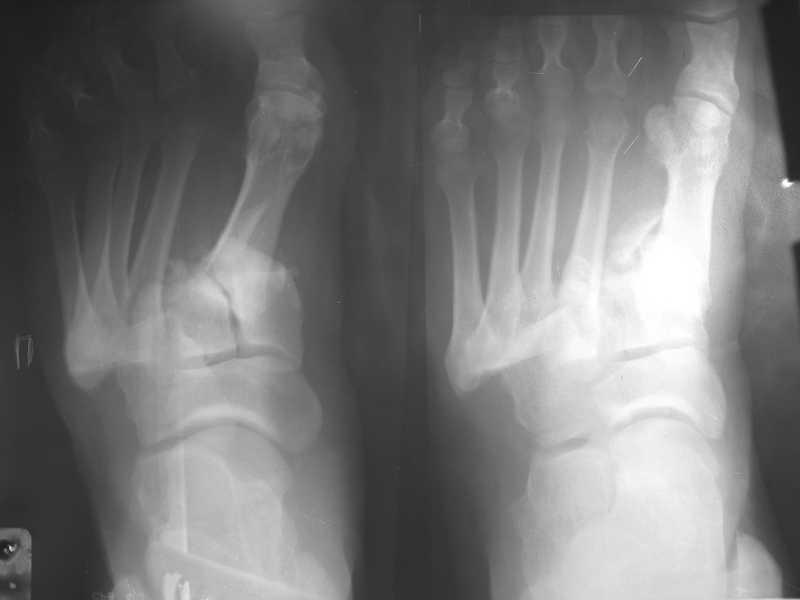

Обратился пациент, мужчина 42лет. для дальнейшего лечения. Травма 11.09., ДТП. 15.09 проведено оперативное лечение фиксаторами.)

(Блокирующий стержень левого бедра - статическая система. Открытое вправление вывиха в суставе Лисфранка и фиксация мет. фиксаторами.) D.S. Переломы диафиза и межмыщелковой области левого бедра, вывих в суставе Лисфранка правой стопы. Состояние после МОС. Через 6 нед. контрольная Ro,( снимки прилагаются).